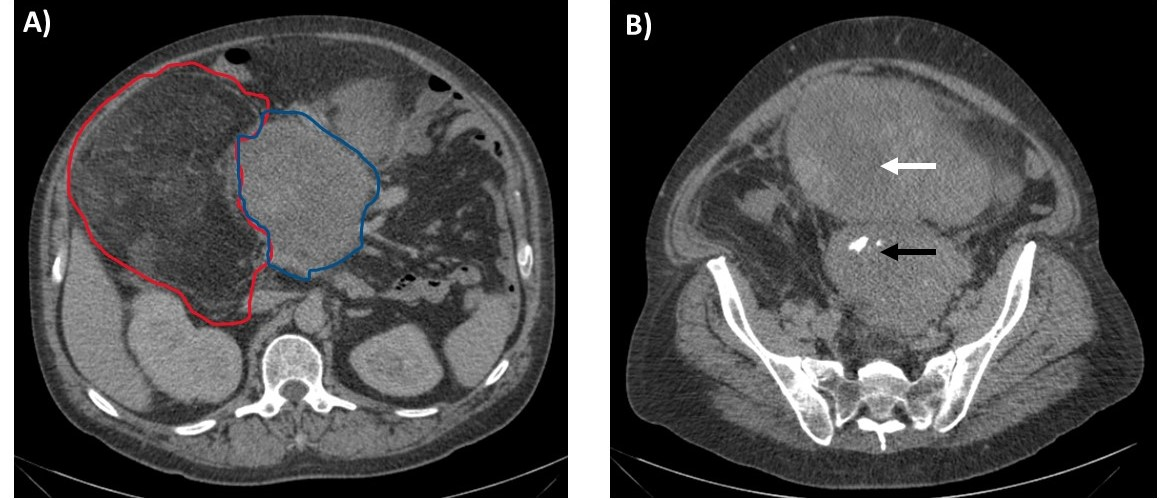

- Completeness of resection (R0, R1, R2) of retroperitoneal soft tissue sarcoma correlates with patient survival.